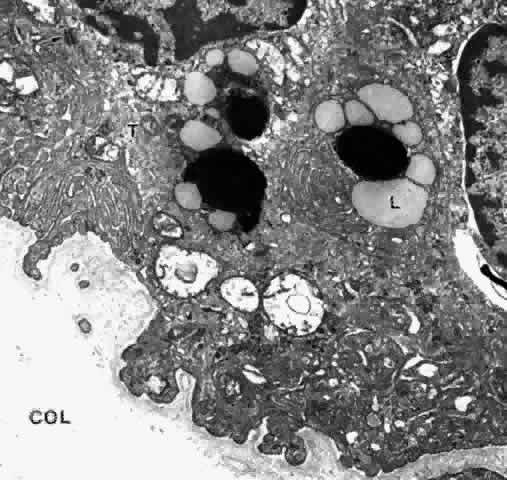

body to the apical PE of the retina. The cytoplasm of the PE cell is more electron-dense than that of the NPE

cell, containing many free ribosomes, actin filaments, and predominantly

cytokeratin-containing intermediate filaments (Fig. 25).26 The mitochondria are smaller and fewer in number than in the NPE, as is

the RER, and the Golgi apparatus is present irregularly. There are large

numbers of rounded and some elliptical melanin pigment granules of

the 0.8 μm to 2 μm size characteristic of neuroepithelium, and

three to four times larger than those of the stromal pigment cells. A

decrease in pigment granules occurs in the PE over the crests of the

ciliary processes from the fourth decade of life. Lipid droplets and complex

lipopigment granules are seen within the cytoplasm during aging (see Fig. 25). The base of the PE cell is markedly infolded, lying on a basement membrane

with that of the fenestrated capillaries in the pars plicata region (Fig. 27).  Fig. 25. Ciliary pigmented epithelial cells in mid pars plana of a young adult. The

cytoplasm is electron-dense with many tonofilaments (T) (intermediate

filaments). Lipid droplets (L) are present around dark lysosomal residual

bodies. Desmosomes connect the cells (arrow). The basal surface

and intercellular junctional areas are markedly infolded, and the basement

membrane is moderately thick. Negative images of collagen fibers (COL) are

seen below, in the dense stroma typical of this region (X 17,500) Fig. 25. Ciliary pigmented epithelial cells in mid pars plana of a young adult. The

cytoplasm is electron-dense with many tonofilaments (T) (intermediate

filaments). Lipid droplets (L) are present around dark lysosomal residual

bodies. Desmosomes connect the cells (arrow). The basal surface

and intercellular junctional areas are markedly infolded, and the basement

membrane is moderately thick. Negative images of collagen fibers (COL) are

seen below, in the dense stroma typical of this region (X 17,500)